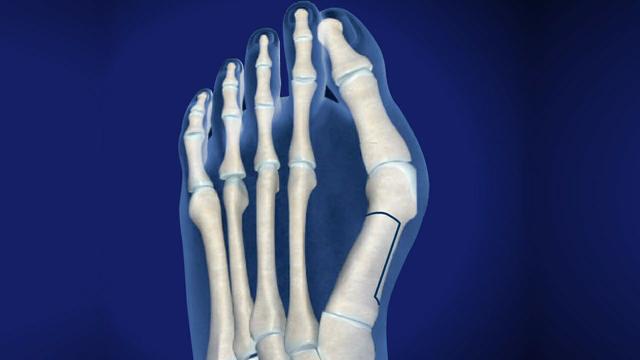

Scarf Procedure

当畸形中等至严重时,Scarf Procedure是常用的选择。从内向外沿跖骨干纵轴截骨。将跖骨头截骨块移向外侧,并用两个螺钉固定。